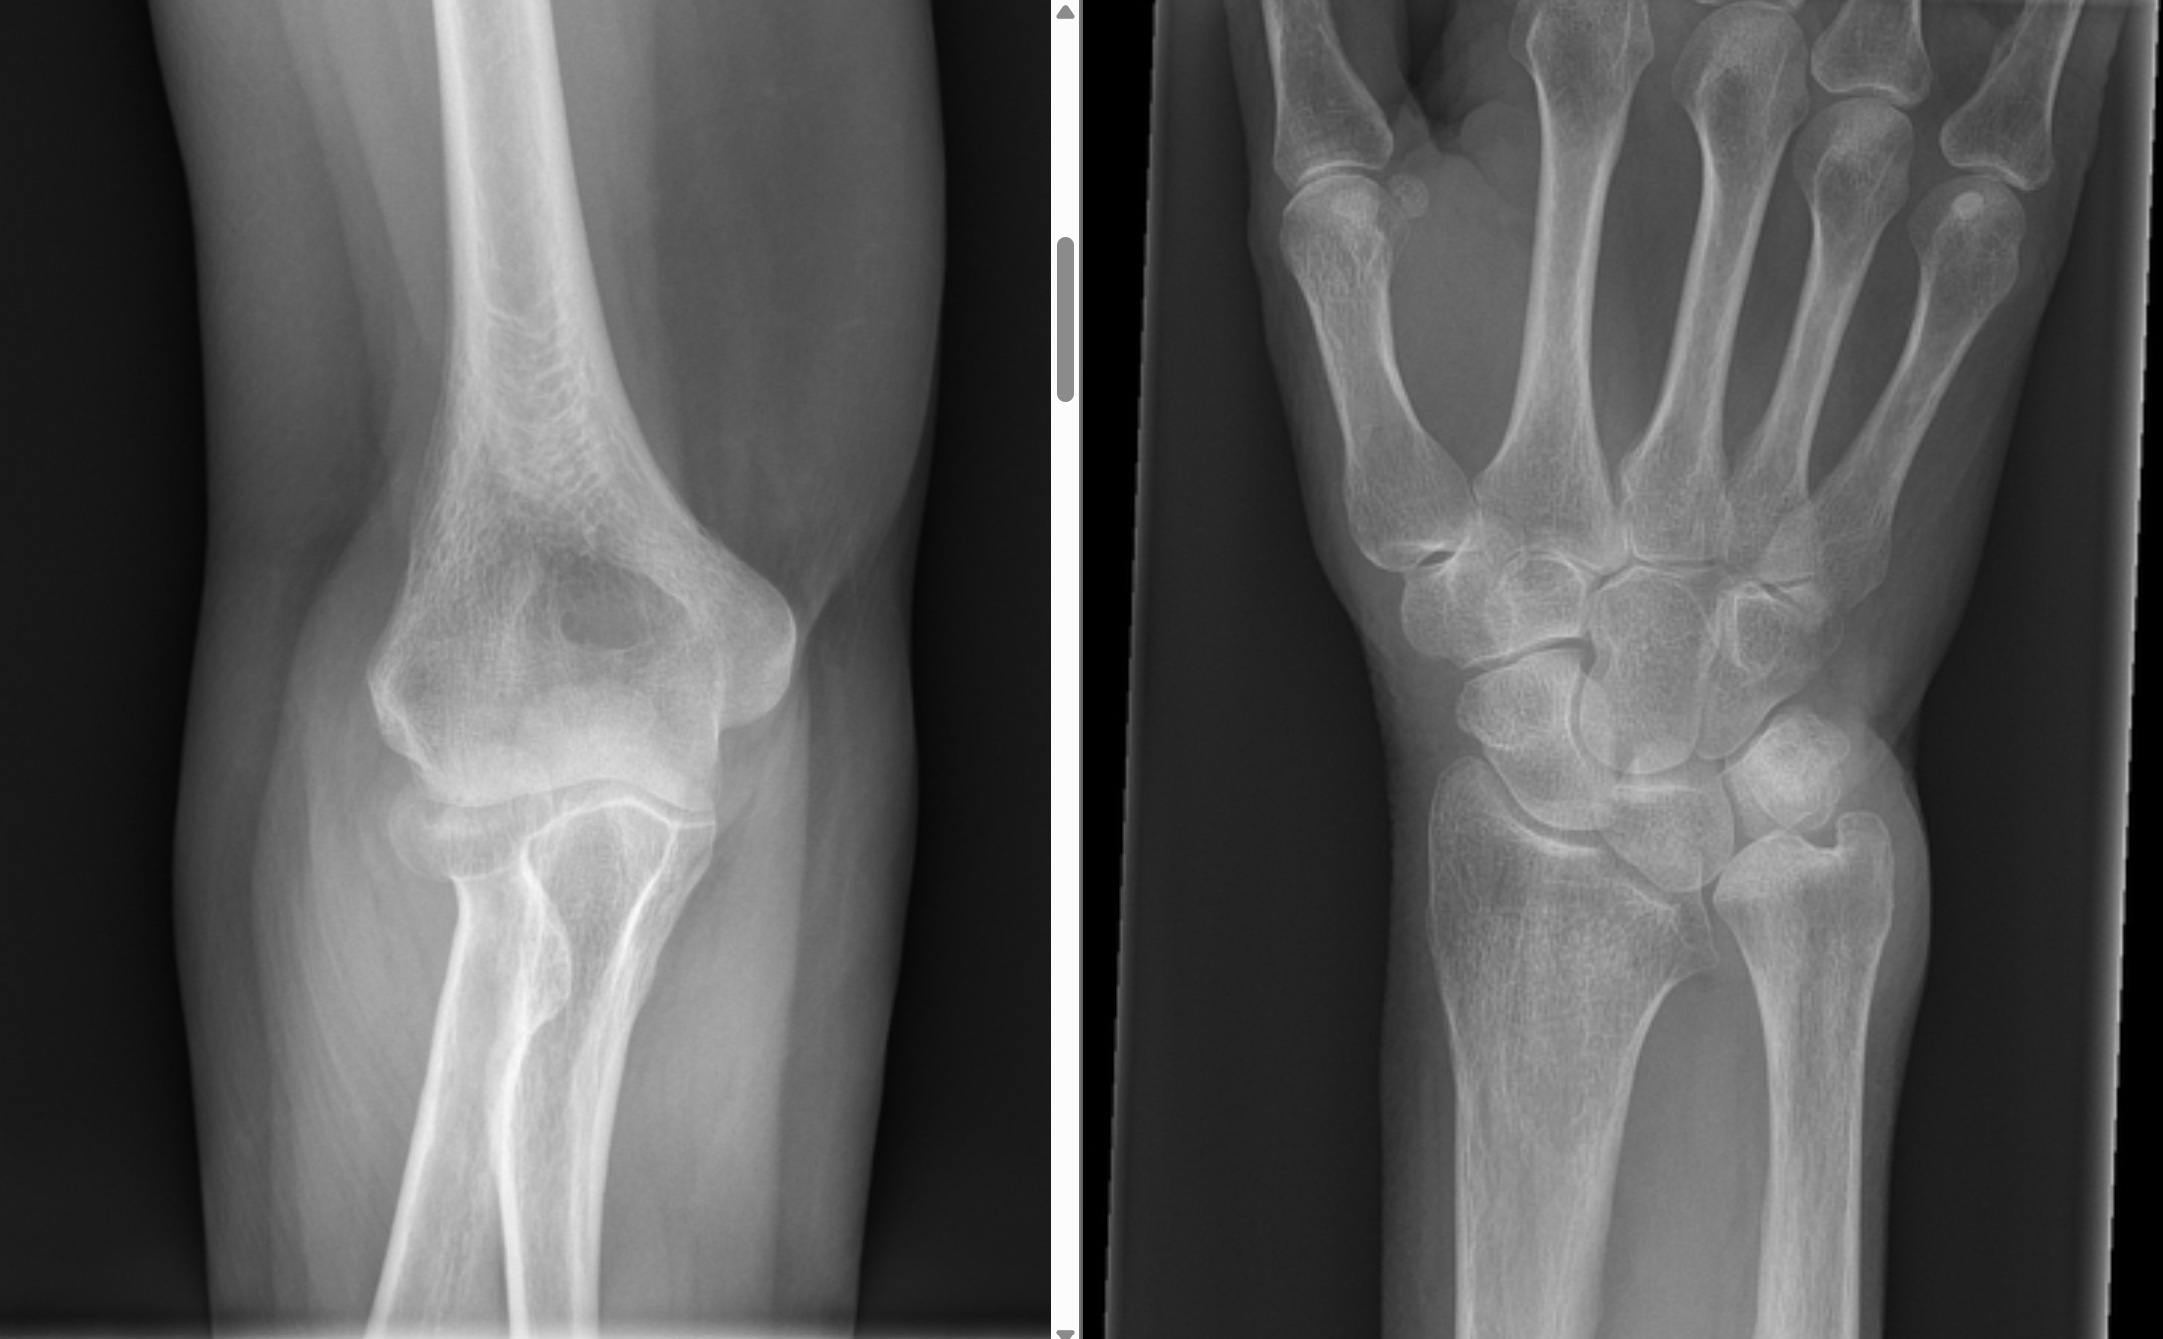

Describe the abnormality demonstrated.

Anterior and posterior fat pad sign indicating a joint effusion, likely from a radial neck fracture

Describe the abnormality demonstrated.

Anterior and posterior fat pad signs, indicating a joint effusion, likely associated with the minimally displaced intra-articular radial head fracture